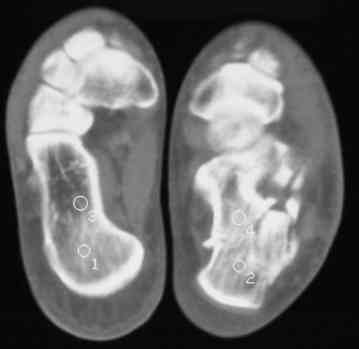

Уважаемые коллеги! Пришел на консультацию больной - "растяжение связок левого голеностопного сустава" полтора месяца назад, поскольку был в морях, на ногу не наступал. Снимки и КТ - в приложении.

Целесообразно Вашему пациенту выполнить подтаранный компрессионный расклинивающий артродез с использованием канюлированных винтов.

52 дня - неудобный срок, особенно учитывая недостаточную нагрузку ноги в плавании. Я обычно пациентам в такой ситуации назначаю препараты кальция и дозированную нагрузку, через 1-1,5 месяца после - оперируем. Операция показана для восстановления оси и высоты пяточной кости, устранения грушевидного расширения ее и вальгусного отклонения,устранения болевого и посттромботического синдромов. Тему лечения осложненных переломов пяточной кости в поздние сроки не освещал в известной Вам монографии сознательно: это одна из глав диссертации моего ученика С.М.Платонова.